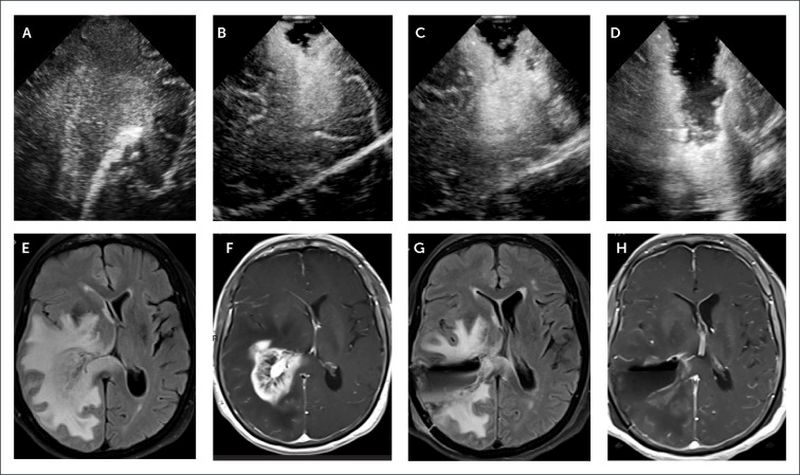

Entre los deterioros se encontraron una mayor reducción en el grosor de la materia gris y un daño tisular en regiones del cerebro asociadas con el olfato. En comparación con los participantes no infectados, los efectos cambiaban entre un 0,2% y un 2%.

También se encontró evidencia de pequeñas hemorragias, daño neuronal y muerte, incluso en personas que no tenían una enfermedad grave.